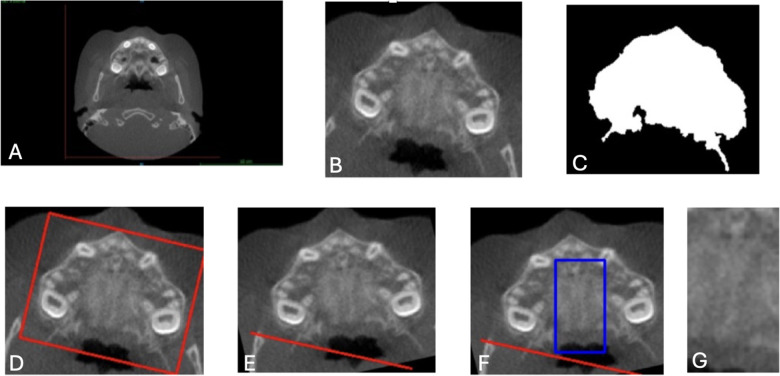

Methods: This study aimed to develop and evaluate a lightweight two-dimensional convolutional neural network (2D CNN) for the automated classification of MPS maturation stages using axial CBCT slices. A retrospective dataset of CBCT images from 111 patients was annotated based on Angelieri's classification system and grouped into three clinically relevant categories: AB (Stages A and B), C, and DE (Stages D and E). A 9-layer CNN architecture was trained and evaluated using standard classification metrics and receiver operating characteristic (ROC) curve analysis.